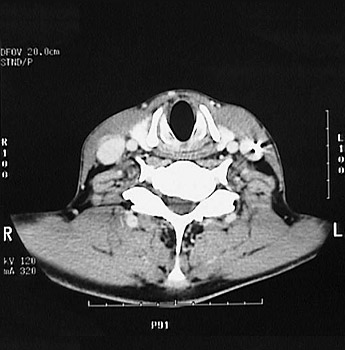

This is a normal axial head and neck CT scan demonstrating the thyroid cartilage and cricoid cartilage and constrictor muscle and subglottis and C5 and spinal canal and internal jugular vein and common carotid artery and trapezius muscle and levator scapulae muscle and sternocleidomastoid muscle.